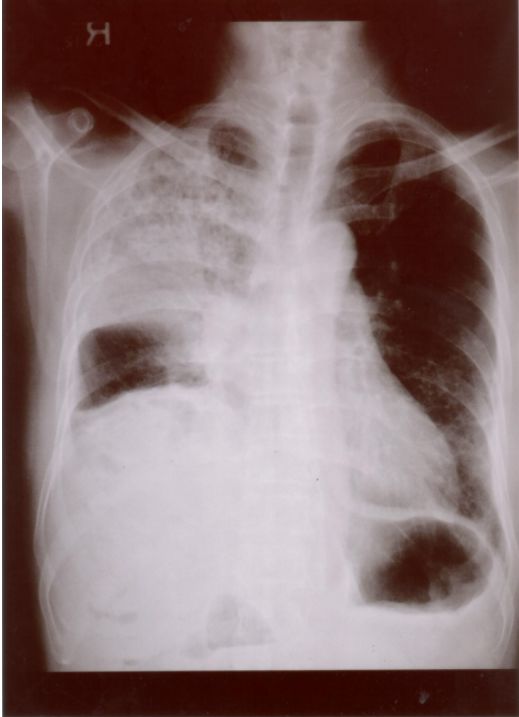

13. 39歲男性有多重性伴侶,因持續發燒及體重減輕3公斤,而且逐漸感到呼吸困難而入院,身體檢查發現口腔有白色珠菌 (Candida)感染,胸腔 X光如圖35 ,血液檢查結果: HIV Test :陽性、血液淋巴球比率: 8%、 CD3:34% 、CD4:0.2%、 CD8:36% 、CD19:4%,肺部灌洗液檢出囊胞蟲(Pneumocystis carinii),下列敘述何者為真?a. 囊胞蟲肺炎 ( Pneumocystis carinii pneumonia ) 典型表現為兩側肺門旁之浸潤,很快迅速進展成瀰漫性兩側肺部浸潤b. AIDS合併囊胞蟲肺炎患者的死亡率為單獨感染囊孢蟲肺炎者之三倍c. 所有囊胞蟲肺炎患者均需住院治療d. 大部HIV合併囊胞蟲肺炎病患的症狀均為突發性咳嗽,高燒而無呼吸困難症症狀e. Trimethoprium-Sulfamethoxazole仍為治療及預防囊蟲肺炎之首選藥物